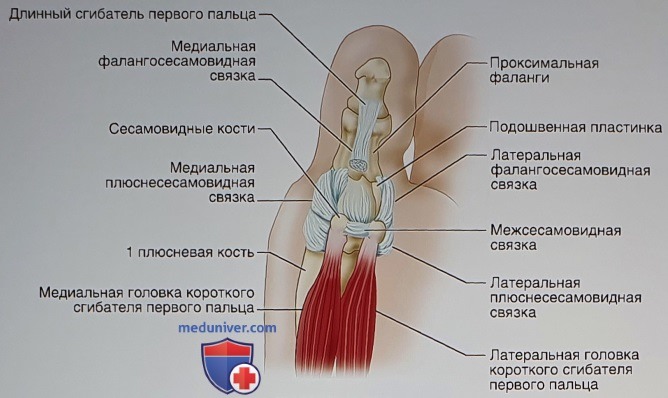

Анатомия: Блоки и сесамовидные кости в деталях